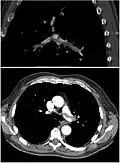

Ventilation-perfusion scintigraphy

(A) After inhalation of 20 mCi of Xenon-133 gas, scintigraphic images were obtained in the posterior projection, showing uniform ventilation to lungs.

(B) After intravenous injection of 4 mCi of Technetium-99m-labeled albumin, scintigraphic images are shown here in the posterior projection. This and other views showed decreased activity in multiple regions.

A ventilation/perfusion scan (or V/Q scan or lung scintigraphy) shows that some areas of the lung are being ventilated but not perfused with blood (due to obstruction by a clot).[19] This type of examination is as accurate as multislice CT, but is less used, due to the greater availability of CT technology. It is particularly useful in people who have an allergy to iodinated contrast, impaired kidney function, or are pregnant (due to its lower radiation exposure as compared to CT).[66][67][68] The test can be performed with planar two-dimensional imaging, or single-photon emission computed tomography (SPECT) which enables three-dimensional imaging.[59] Hybrid devices combining SPECT and CT (SPECT/CT) further enable anatomic characterization of any abnormality.[69]